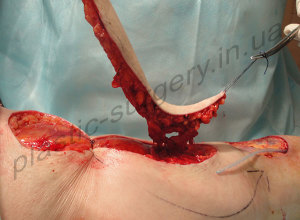

В клинике определена зона рассечения и иссечения рубцов в подколенной области, где после устранения контрактуры и выведения конечности в положение полного разгибания сформировался раневой дефект, площадью до 4 х 9 см., который не может быть закрыт путем сближения краев раны или выполнения стандартной Z-пластики (Рис. 11). Методом допплера лоцирован третий перфорант глубокой артерии бедра, выходящий на заднюю повехность кожного покрова бедра в его нижней 1/3) и намечен дизайн кожно-подкожно-фасциального перфорантного пропеллер лоскута (PPPF) на базе названного перфоранта (Perforator of the Profunda Femoris Artery Perforator – PFAP-3). После полной дессекции PFAP-3 лоскут поднят на ножке, включающей обозначенный перфорант, проведена его визуализация и определена жизнеспособность самого лоскута (Рис. 12).

Рис. 11. Цифровое интраоперационное фото раневого дефекта после иссечения рубцов, устранения контрактуры, выведения нижней конечности в положение полного разгибания и выкраивания островкового PFAP-3 лоскута (слева).Точка проекции перфоранта и поворота лоскута (point pivot) обозначена крестом.

Рис. 12. Цифровое интраоперационное фото раневого дефекта после полной дессекции и подъема кожно-подкожно-фасциального островкового PFAP-3 лоскута, определение его жизнеспособности (справа).